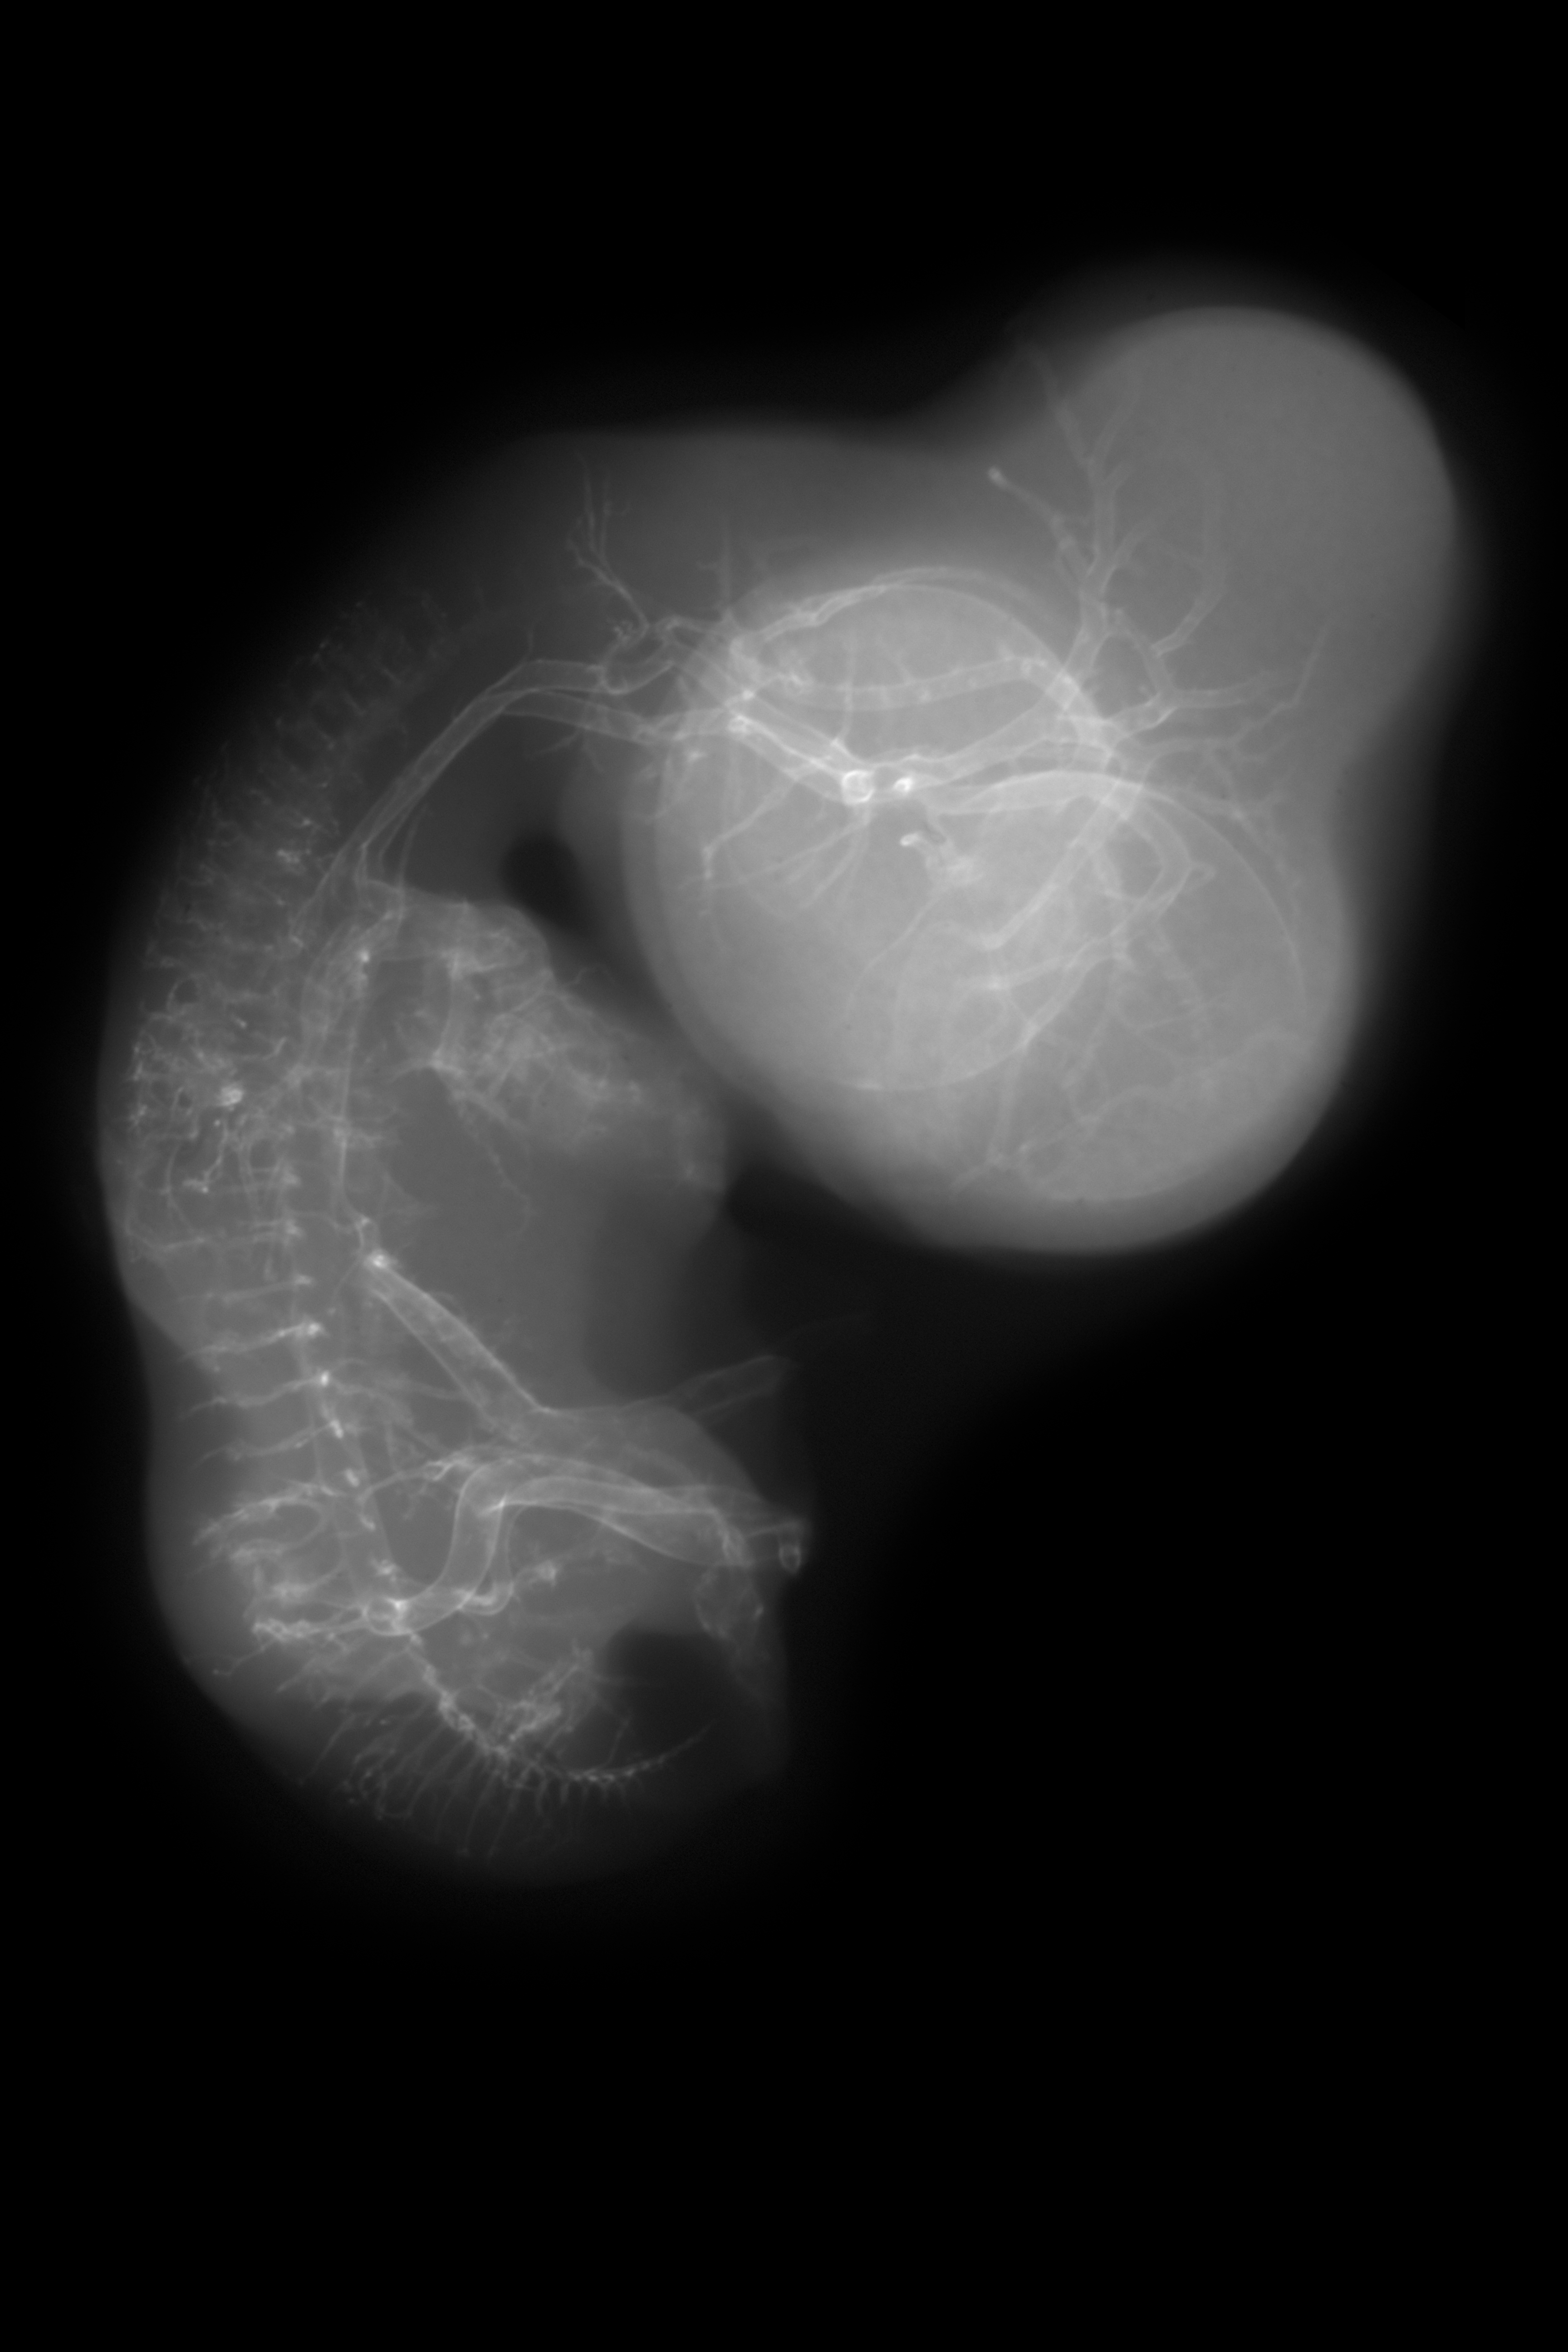

X-Ray Micrographs